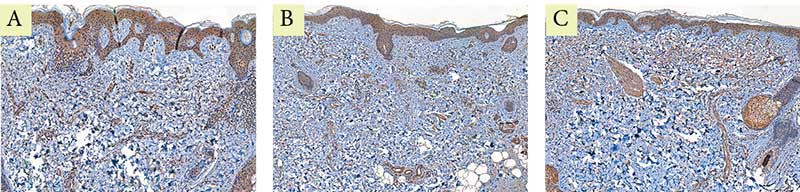

Рис. 4. Пациентка Л. Экспрессия маркера коллагена I типа: A – до процедуры; B – через месяц после процедуры; C – через пять месяцев после процедуры